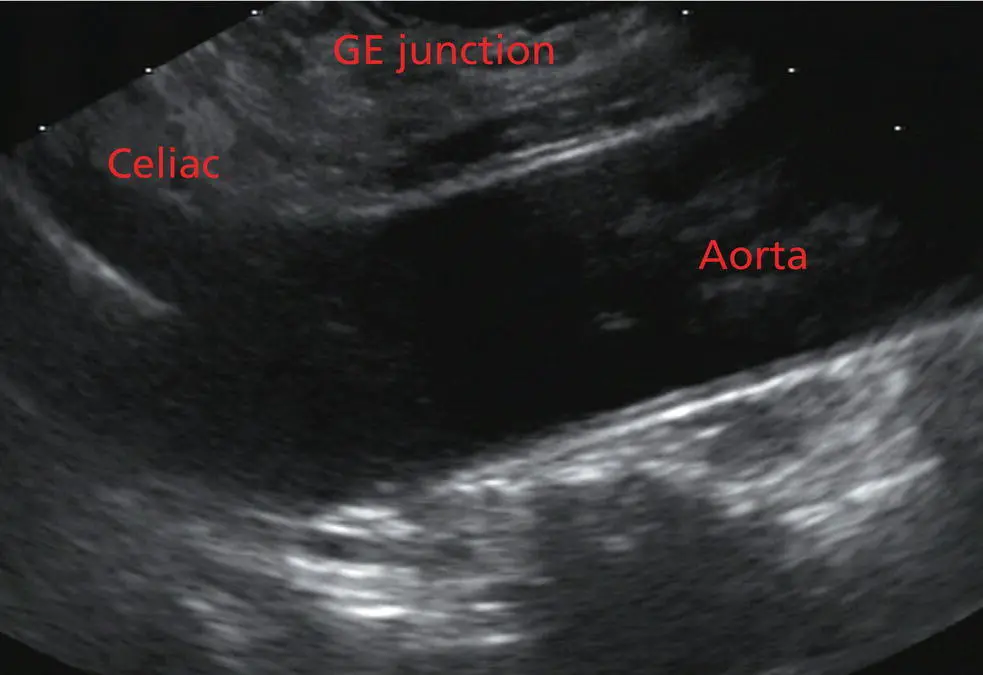

The origin of the celiac artery ( Figure 2.11) is identified and then the scope can be withdrawn. This is the standard reference point for the beginning of the exam during withdrawal. Examination of the extraesophageal and thoracic structures is more time consuming than the radial approach as this echoendoscope’s narrow focal point has to be torqued back a further 180 degrees to cover the same field of examination. This is done by withdrawing the scope at increments with constant back and forth torque.

Figure 2.11 Linear array image at the level of the celiac artery.